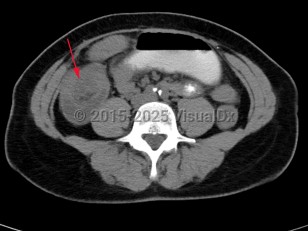

Intussusception is a telescoping or invagination of a part of the intestine into the lumen of an adjacent segment. Intussusception can present with variable severity. It can present with bowel ischemia and perforation with need for emergent surgical intervention, or it can present as relaxing / remitting abdominal pain of unclear etiology with intermittent symptoms and no signs of systemic illness. Jejunojejunal, jejunoileal, ileoileal, ileocolonic, and colocolonic are all types of intussusception that can occur, with the majority involving the small intestine.

Initial management requires ensuring hemodynamic stability, as many patients are dehydrated, and assessing concern for bowel perforation, which could require broad-spectrum antibiotics and urgent surgical intervention. Air or barium enemas can be both diagnostic and therapeutic. However, intussusception will frequently recur, in which case surgical resection is often required. Further imaging (ie, small bowel x-ray series, CT or MRI abdomen) can be utilized to identify the etiology if it is unknown based on presenting symptoms and a barium / air enema.